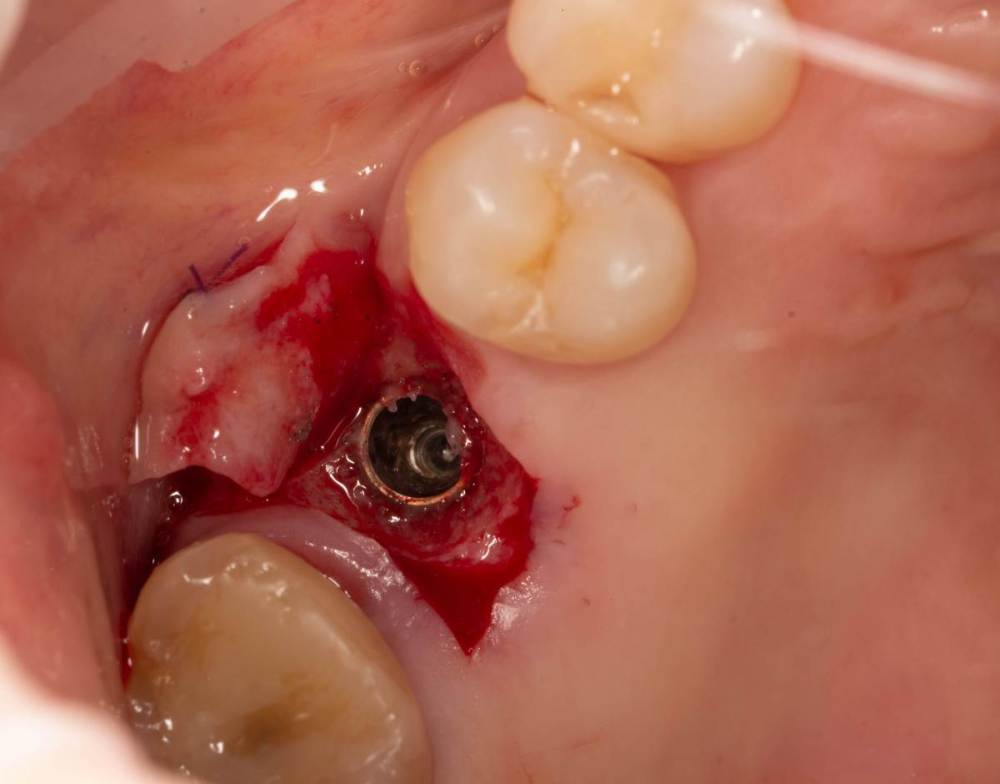

Женька Опубликовано 3 октября, 2022 Поделиться Опубликовано 3 октября, 2022 Открывал я снова тут имплантат roll техникой. И взбрело в голову, мол нёбно то много отрезал. Решил попробовать сделать скользящий нёбный лоскут. Как вы уже наверное догадались, ничего из этого не вышло . Лоскуток нёбный поначалу вроде даже смещался скользя, но далее превратился в СДТ маленький, который пришлось с определёнными трудностями возвращать хотя бы обратно на место (хорошо хоть не засосало в слюноотсос). Собственно вопрос, где и как можно данной методике научиться? может почитать где-то можно. У первоисточника хотелось бы, конечно) но трудно осуществимо. 1 Ссылка на комментарий